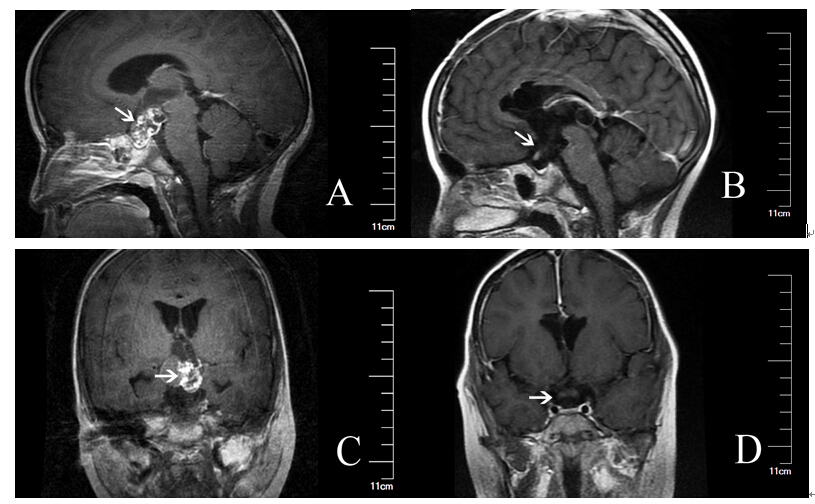

注:图A、C为颅咽管瘤患者术前头核磁影像学表现;图B、D为颅咽管瘤患者术后核磁影像学表现。箭头指示处为肿瘤位置。